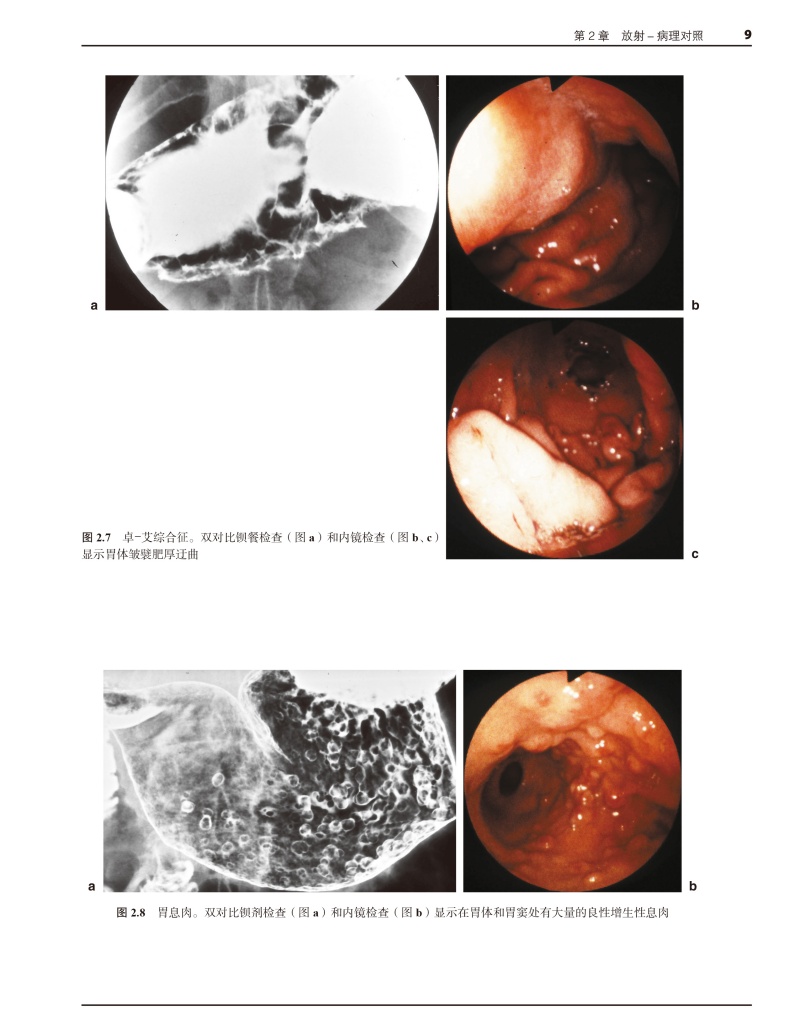

本书由英国剑桥大学医学院A.H.Freeman先生和E.Sala女士主编,是一部基于多学科诊治框架的胃十二指肠放射学专著。该书对胃、十二指肠疾的解剖、生理、病理、内镜、超声内镜、钡餐造影、CT、磁共振成像、同位素检查和介入放射学等方面进行了系统、深入的阐述,并结合具体案例对重要的临床问题进行剖析和总结。本书由中山大学附属第五医院张亚琴教授、暨南大学附属华侨医院史长征教授、江门中心医院崔恩铭教授和南方医科大学南方医院吴元魁教授共同主持和消化内科、胃肠外科、血管介入、核医学科、影像科医师参与,历经3年对原著进行了翻译。是一部这是一部具有很高学术价值而且实用性很强的专著。

结合具体案例对胃、十二指肠疾的解剖、生理、病理、内镜、超声内镜、钡餐造影、CT、磁共振成像、同位素检查和介入放射学等方面进行系统、深入的阐述